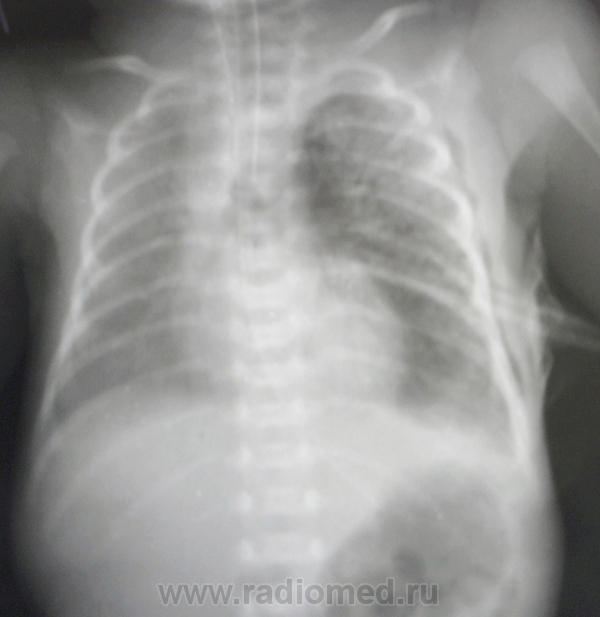

На первых снимках левосторонний пневмоторак; затем дренирование, пневмоторакс, практически, разрешился, признаки РДС  новорожденных (отек).

недоношенность ведь не обязательно сопровождается РДС... причины спонтанки не выяснили, запоздали с дренированием, малышка около 12 часов была с коллабированным левым легким. Думаю, что незрелость легочной паренхимы да смещение средостение с большим пневмотораксом явились причиной. Так ли?

На последих 3-х снимках явления подкожной эмфиземы. ИМХО: смещение средостения и коллабирование лёгкого являются следствием пневаторакса, причина которого, вероятно в незрелости лёгочной ткани.